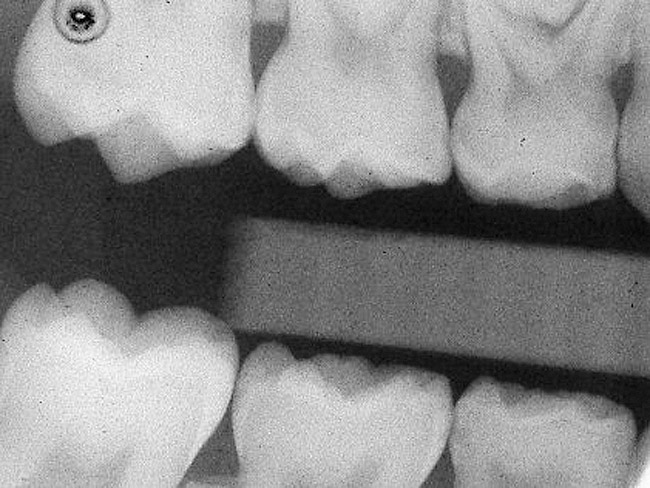

Caries infiltration is indicated for all age groups, up to the first third of dentin (D-1) (Figure 2). It is especially advantageous in interproximal areas, where a relatively large ratio of healthy hard tissue must be removed to eliminate carious tissue. Infiltration replaces hard tissue lost due to demineralization (to a maximum of 800 µm) with a low-viscosity resin, creating a barrier to further diffusion of carbohydrates and organic acids within the hard tissue, not on the tooth surface. This barrier stabilizes and effectively blocks the caries without changing the anatomic shape or appearance of the tooth.85 Additionally, treated lesions lose their whitish opaque color and blend with surrounding natural enamel, which is especially esthetic in the smooth surface type of lesions often found when fixed orthodontic appliances are removed (Figure 3 and Figure 4).

Figure 2  Preoperative radiograph showing mesial incipient lesion on tooth A.

Figure 2